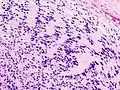

Micrograph of a schwannoma showing both a cellular Antoni A area (top) and a loose paucicellular Antoni B area (bottom). HE stain.

Verocay bodies are seen histologically in schwannomas.